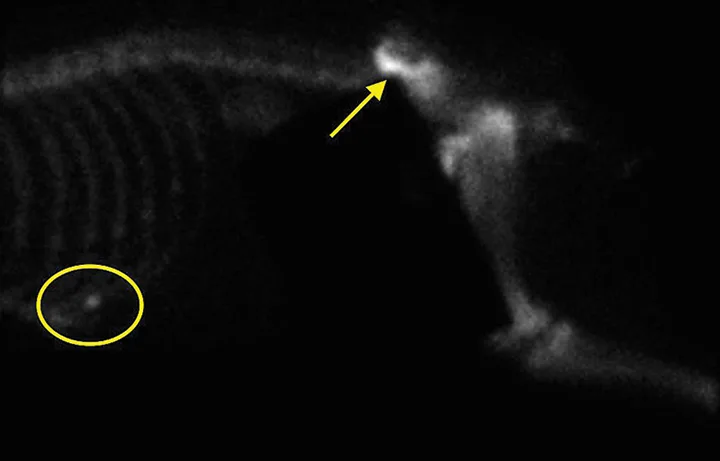

FIGURE 1

Axial (A) and coronal (B) CT images from the patient. An aggressive bone lesion arising from the left ilium, with extension to the surrounding soft tissues, can be seen.

Diagnosis

CBC, serum chemistry profile, and urinalysis results were unremarkable. Three-view thoracic radiographs showed no evidence of gross metastatic disease. A CT scan of the chest, abdomen, and pelvis showed an aggressive bone lesion of the left ilium, compatible with osteosarcoma, with tumor extension to the surrounding soft tissue (Figure 1). A full-body bone scan was performed. Static images were obtained 2 hours after intravenous injection of Tc99m-MDP. There was marked uptake in the area of the primary tumor (ie, the left ilium). There was also a possible metastatic lesion in the left costal cartilages; however, careful review of the CT scan showed that the increased uptake of radiopharmaceutical at that site was most likely consistent with old trauma rather than metastatic disease (Figure 2).